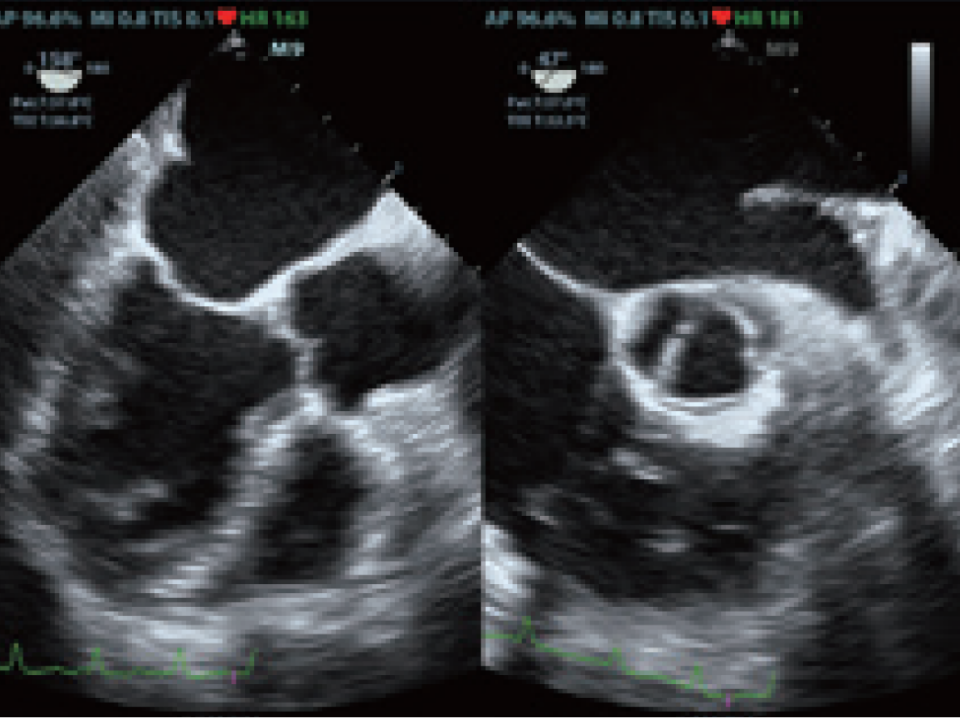

Mehr Mobilit?t muss nicht zu Lasten der Leistung gehen. Der M9 z?hlt mit seinen hoch?entwickelten Funktionen, die ĂŒblicherweise nur in schweren Standger?ten zu finden sind, zu den fortschrittlichsten Premium-Sonographiesystemen im Laptop-Format. Dank der Ultraschallplattform mQuadro hebt das M9 den Branchenstandard auf ein Topniveau.

- Schneller, besser, M9